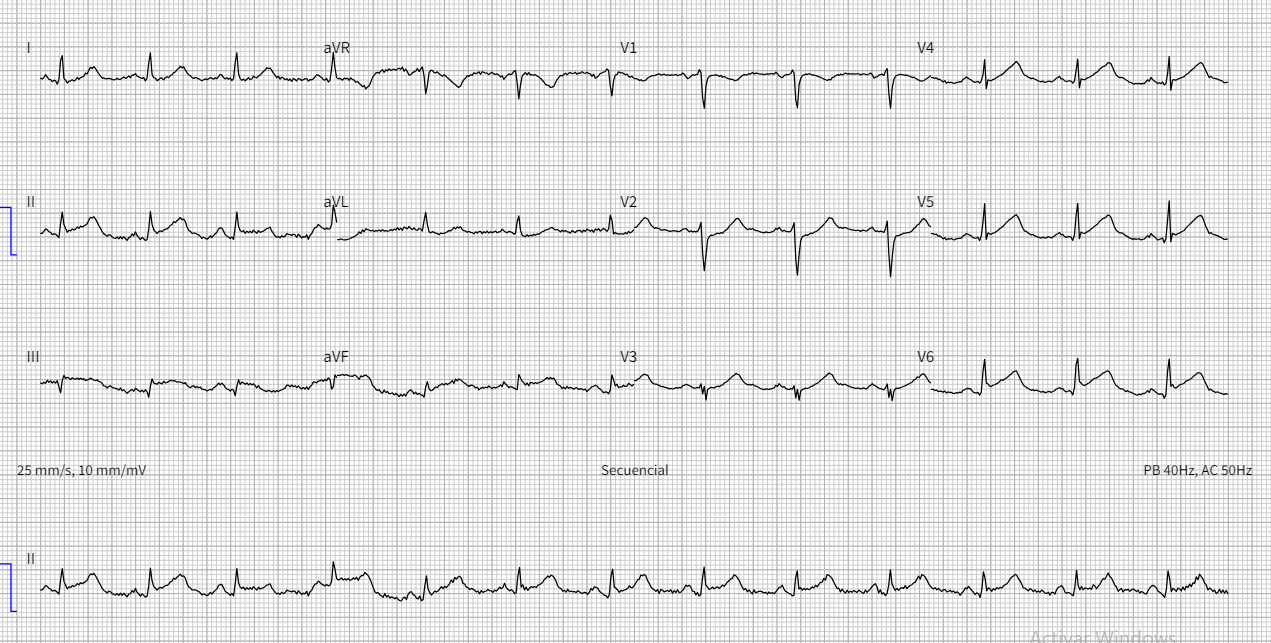

Upon admission to our center, the patient continued to experience precordial pain. She was hypertensive, normocardic, and showed no signs of heart failure. ECG showed ST-segment elevation in the inferior, anterior, and lateral leads. Emergency coronary angiography was performed after dual antiplatelet therapy and intravenous nitroglycerin were administered. At the time of the study, the patient was asymptomatic, ECG changes had resolved, and no significant stenoses were found.

Figure 1. ECG on admission, showing ST-segment elevation in the inferior and anterolateral leads.